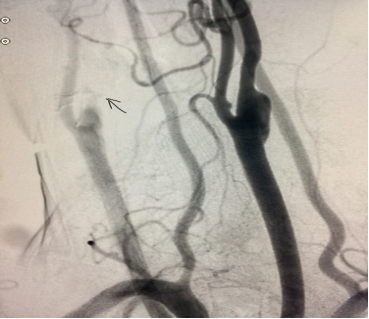

太极高手戴某,因为“突发言语含糊伴右侧肢体偏瘫三小时”到我院急诊,入院一小时后入导管室主动脉弓造影示右侧颈内鼠尾征-一起始部闭塞,左侧可见狭窄明显。

进一步右侧颈总动脉造影示典型鼠尾征